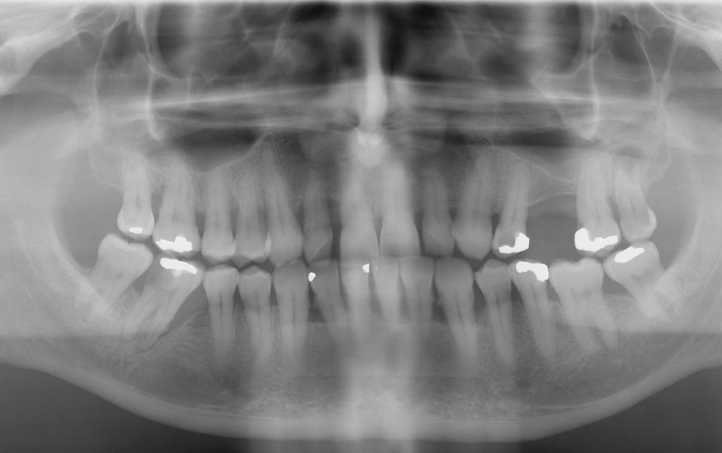

- Regular Dental Check-ups and X-rays: Your dentist can spot a deep cavity or a crack before it reaches the pulp. They can also see early signs of a chronic, asymptomatic abscess on an X-ray (a dark spot at the root tip) and treat it before it becomes painful. The American Dental Association stresses the importance of these regular visits for preventive care.